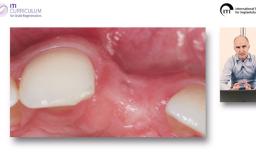

Implantatverlust mit Defektsituation: Erneute Implantation oder Alternativtherapie?

Dieter Weingart

Basierend auf diversen Studien und eigener klinischer Erfahrung stellt Dieter Weingart seine Erkenntnisse und Schlussfolgerungen zum Thema Implantatverlust mit Defektbildung vor. Er illustriert das Thema mit eigenen klinischen Fällen inklusive Langzeit-follow-ups.